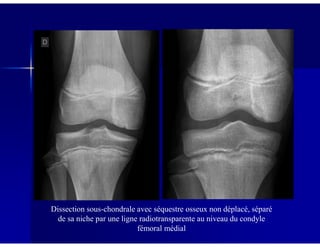

Dissection sous-chondrale avec séquestre osseux non déplacé, séparé

de sa niche par une ligne radiotransparente au niveau du condyle

fémoral médial